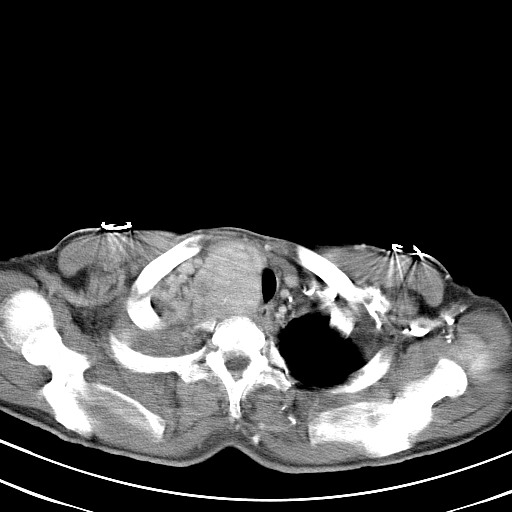

以下是引用汪涛同志在2007-8-2 0:40:00的发言:[br]病变虽然广泛,同时侵及双侧纵隔,但是无论左侧和右侧上下观察都是与右侧颈部甲状腺相延续的,而且强化幅度基本一致,又同时具有恶性病变病变的某些特征:肿块过大且密度不均,部分层面与正常纵隔结构分界不清,结合病史已有两年,考虑:胸内甲状腺肿恶变可能。[br]